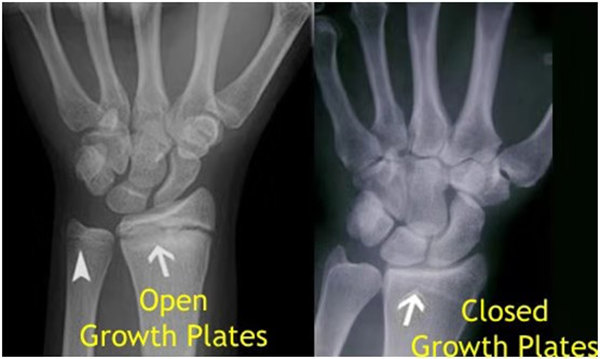

我們都知道,人體的高矮是由骨骼的生長(zhǎng)發(fā)育決定的,特別是下肢長(zhǎng)骨。長(zhǎng)骨呈長(zhǎng)管狀,在長(zhǎng)骨的兩端有一種專(zhuān)管骨骼生長(zhǎng)的骺軟骨,它與干骺端之間有一盤(pán)狀軟骨結(jié)構(gòu)稱(chēng)為骺板(線),在幼兒的X光片上表現(xiàn)為一條較寬的透光帶。 (見(jiàn)下圖)

未成年時(shí)隨著年齡的增加骺軟骨端不斷骨化,骨骼就不斷增長(zhǎng)。當(dāng)骨骺線完全閉合時(shí)骨骼就停止生長(zhǎng),個(gè)子也就不再增長(zhǎng)了。一般骨骺端完全閉合的年齡是18~20歲左右。